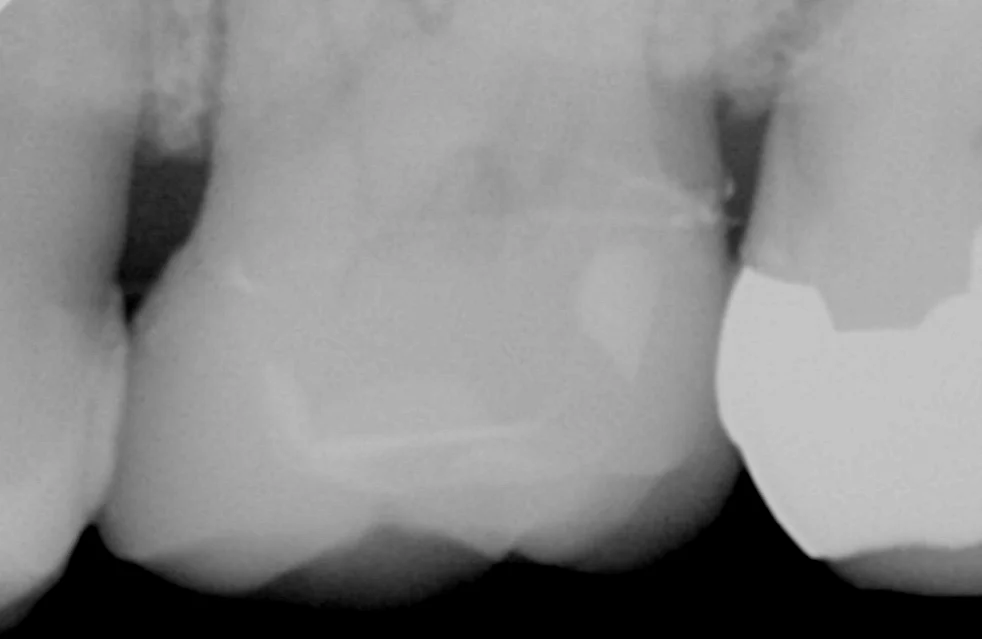

セメントの除去した後に取り残しが不安な場合はレントゲンも撮影することがありますが、その時の写真がこちらです。

後ろの歯との間に少しセメントが残留していたので、戻った後に完全に除去し、終了しました。

また適合が非常に良好なのもこのレントゲンで確認できる部分ですね。